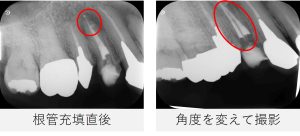

- その後、根管充填を行い、仮封しました。

- レントゲンを撮影し、根管充填の状態が良好であることを確認しました。

根管充填後は、症状の有無だけでなく、レントゲンやCT画像を用いて根の先や側面の骨の状態を確認しながら経過を観察していきます。

- レントゲンおよびCTで確認したところ、根の先や側面に見られていた透過像は縮小し、骨の回復傾向が確認されました。